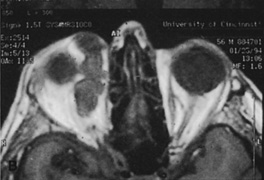

Valuable information about the nature and extent of an orbital pathologic process is provided by imaging studies such as computed tomography (CT) scan, magnetic resonance imaging (MRI), and orbital echography. Better spatial resolution, ready accessibility, and lower cost make CT the preferred choice for orbital imaging in most cases. Orbital fat provides a natural contrast between most adjacent orbital structures on CT scanning, and orbital bones are visualized well. Computed tomography is essential for evaluation of the orbital bones because they cannot be imaged with MRI. Direct coronal or sagittal images are important to identify the relationship of a lesion to the optic nerve so that the surgical approach can be planned to avoid traversing the optic nerve (Fig. 1).

Fig. 1. A. Axial CT scan demonstrating a large, well-encapsulated lesion in the orbital apex. Coronal (B) and sagittal (C) scans demonstrate that the mass lies inferior and medial to the optic nerve within the intraconal space. This information is useful in planning the surgical approach to the mass, which should avoid traversing the optic nerve.